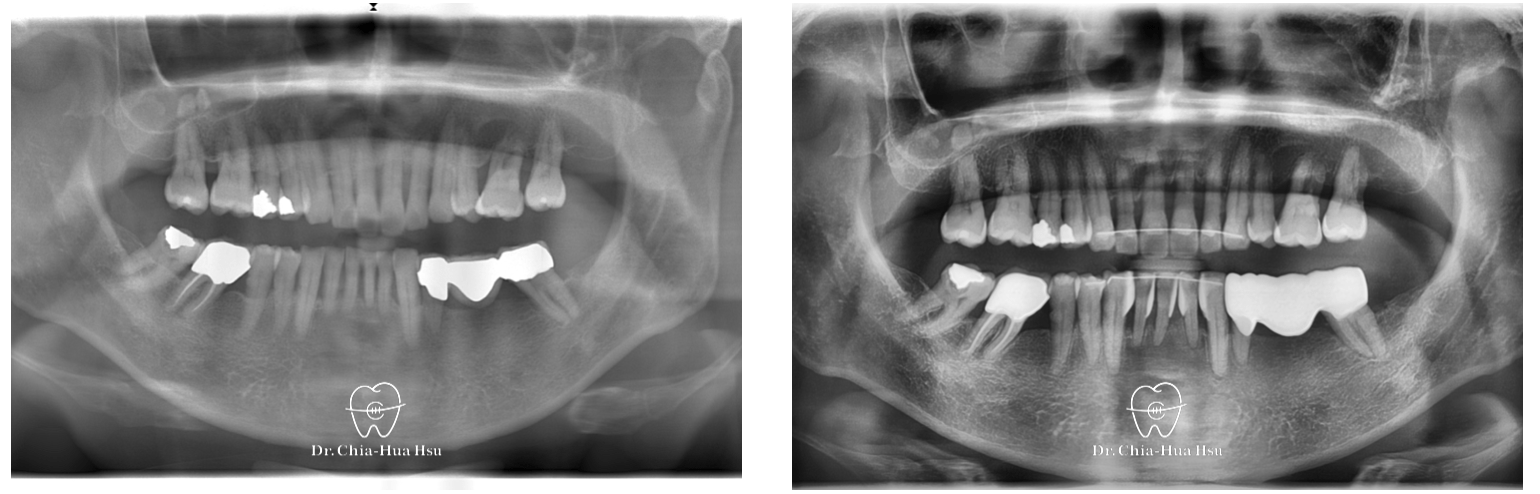

• 治療方式:在病患牙周治療結束後,與患者討論治療方案,最後使用對牙周健康友善的隱適美治療,並搭配上顎骨釘的使用,來改善患者的暴牙與齒列不正。後續也透過美學樹脂補牙來處理患者下顎門牙黑三角縫的問題。

• 治療時間:3 年 2 個月。

• 治療結果:在與牙周病科醫師、牙體復形科醫師的協同治療下,改善患者暴牙和齒列不正,恢復患者的牙周健康與美觀。

治療前

治療後